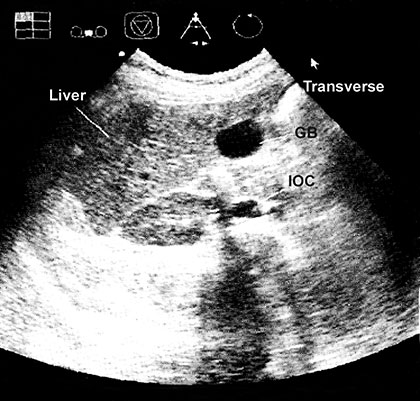

Effect of Tissue Acoustic Impedance

Structure of differing acoustic impedance (such as gall-bladder and liver) are much easier to distinguish from one another than structure of similar acoustic texture (e.g. liver and kidney) (Fig. 1.10).

Echoes are not detected if no difference in acoustic densities are encountered. Homogenous fluid (urine and cyst content, but also ascites and pleural effusion) are seen as echo free (black) structure, e.g. gallbladder and hepatic vessels (Fig. 1.11).

Fig. 1.10: Transverse section of liver, gallbladder and right kidney are shown in the subcostal view